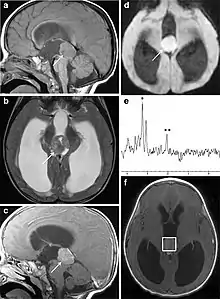

Several imaging methods can be used to diagnose pineoblastoma. Initially, urgent CTs are recommended, followed by MR imaging.[13] CT will show large, multilobulated masses with heterogenous contrast enhancement and peripheral calcification of the pineal gland.[4][3] On MRI, pineoblastomas again appear as masses with heterogenous enhancement. They often appear hypo- to isointense on T1 and slightly hyperintense on T2-weighted images. Some areas of necrosis or hemorrhage may be seen as well. PET-CT has also been used in diagnosis, and shows increased uptake of fludeoxyglucose with pineoblastomas compared to other pineal masses.